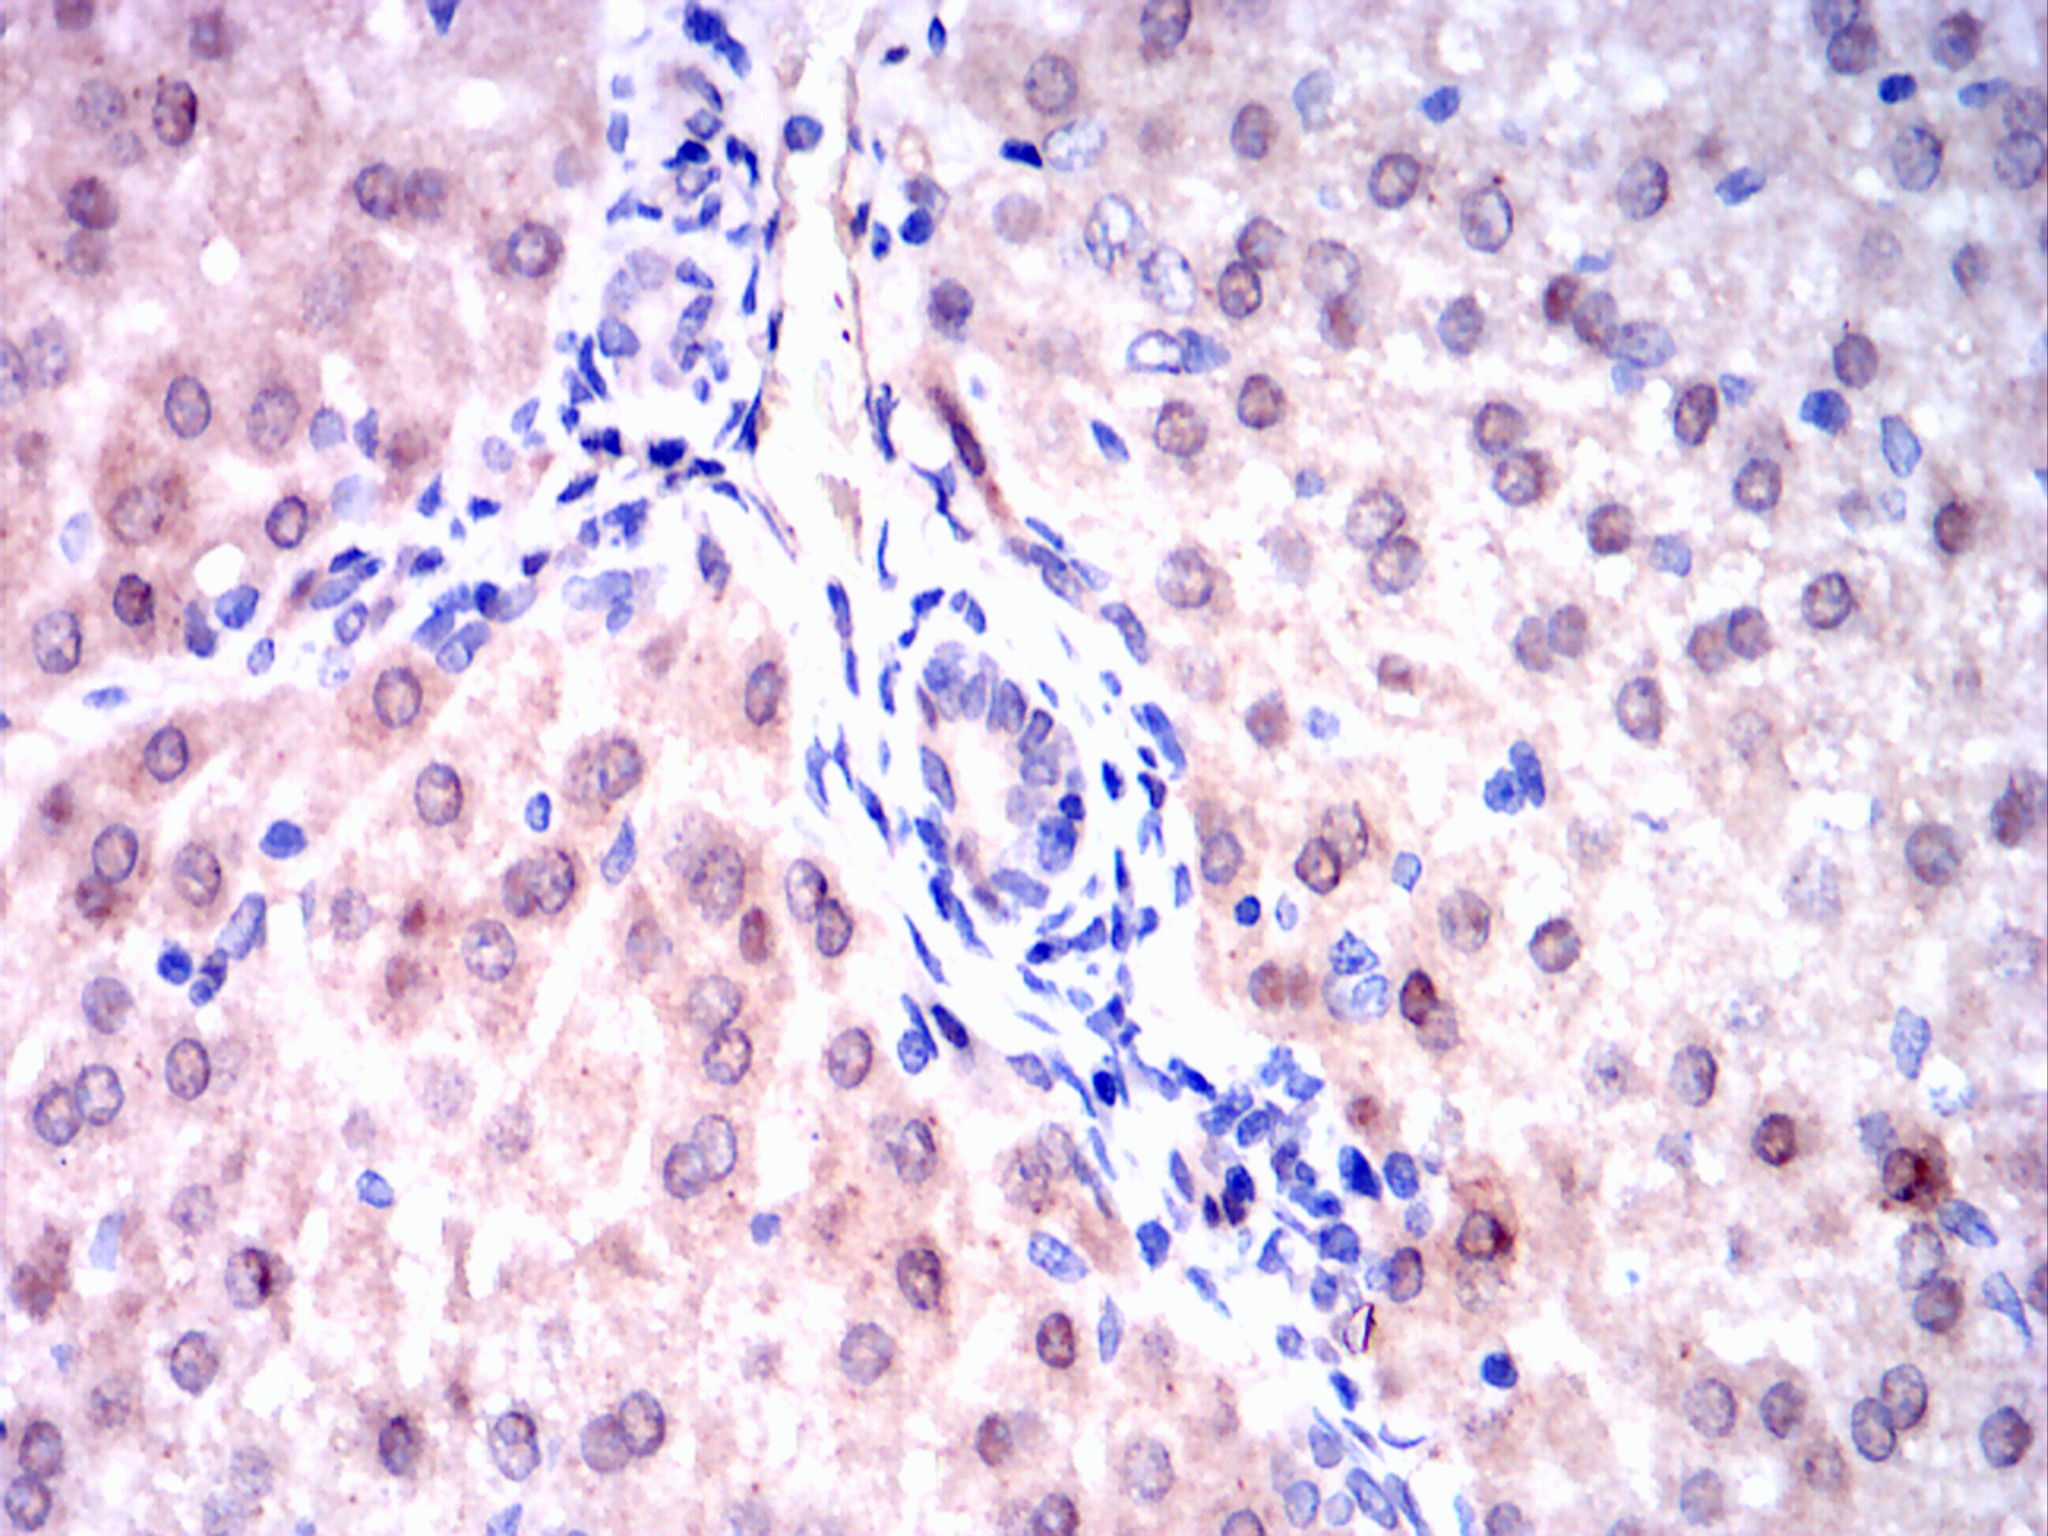

Immunohistochemical analysis of paraffin-embedded esophageal cancer tissues using Visfatin(PBEF) mouse mAb with DAB staining.